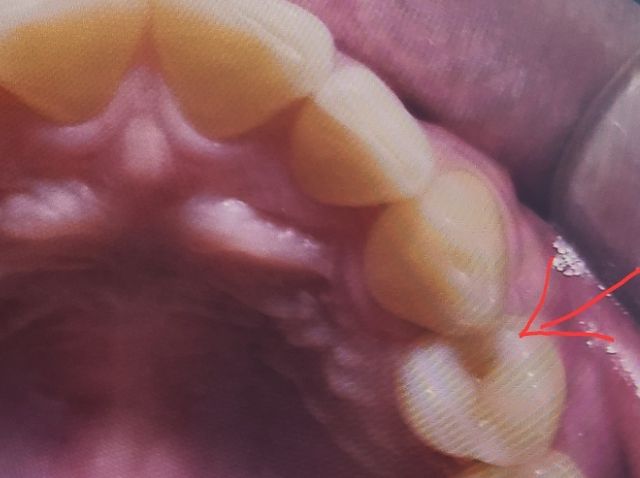

• 다른 선생님께서 애써 하신 것에 안좋은 얘기를 하기가 좀 조심스럽습니다만, 솔직하게 말씀드리겠습니다. 혹시나 질문자분께서 전달을 하게 됐을 때 오해가 없길 바랍니다. 치료당시 어떤 상황이었는지는 모르겠지만 레진을 메꿀 때부터 모양을 잡은 후에 굳혔어야 했는데 이미 저렇게 굳혀버려서 여기서 더 다듬을 수도 없네요. 아예 새로 하시는게 나을 것 같습니다. 잇몸쪽 밑동부분부터 치아면과 이어지게끔 부드럽게 했어야 했는데 아예 네모모양으로 돼버렸네요. 물론 전문가인 치위생사선생님이 치실질을 하실 땐 잘 들어갈 수 있지만, 스스로 하려면 직접 눈으로 보이지도 않는 곳인데 치실질을 잘 할 수 있게끔 만들어주셨다면 좋았을텐데 왜 저렇게 하셨는지 잘 모르겠네요. 당연히 치실이 찢어질 수 있는 상태입니다. 저렇게 메꾸면 음식물을 잘 뺄 수 없고 그로 인해 잇몸도 부을 수 있고 떼운 하방으로 충치도 생기기 쉽습니다. 아마 치과에서도 당시 상황에서 최선을 다하셨을거고 저렇게 하신 것도 나름 이유가 있을 수 있다고 생각합니다. 치료받으셨던 치과와 원만히 해결이 되길 바랍니다...

1. 인접면 컨택이 아주 빡빡하게 되었다면 치실이 잘 안들어갈 수도 있습니다. 얇은 형태의 치실을 사용하시거나, 사이즈 제일 작은 치간칫솔을 사용해보시기 바랍니다.

2. 설명 들으신 것처럼 불편증상이 생기면 다시 인레이로 바꿔줘도 좋을 것 같습니다. 옆면 충치 레진치료는 어느정도 한계가 있습니다.